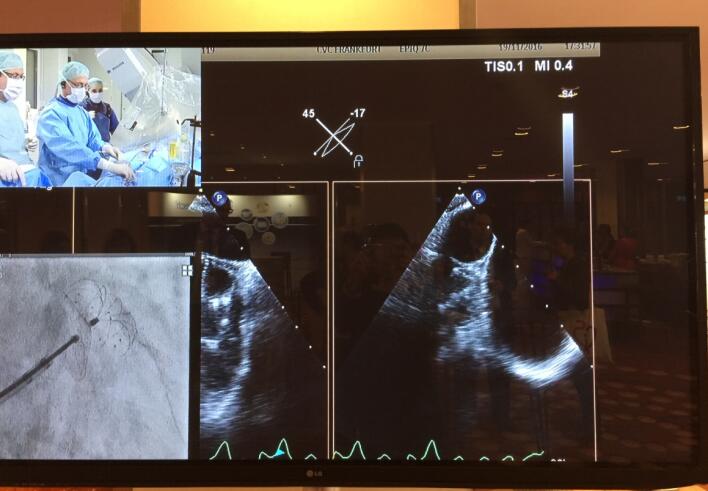

手术直播一直是LAA CSI Focus左心耳专题会议的亮点。本届会议共向现场直播了8台手术,其中两台手术使用了J9集团国际科技LAmbre™左心耳封堵器系统。11月19日上午,大会主席,来自德国法兰克福心血管中心的Horst Sievert教授和来自香港的林逸贤医生使用LAmbreTM 左心耳封堵器系统成功完成一例高难度的左心耳封堵手术。

当时,接受该手术的患者已麻醉就绪,超声波影像显示其左心耳形态为多叶型,且左心耳开口尺寸较大。会议现场对该病例的器械选择讨论异常激烈,场内多位专家讨论表示该患者适合使用LAmbre™左心耳封堵器进行封堵,也有部分专家坚持自己的学术主张。对于该病例,主要术者Horst Sievert教授首先尝试使用其他品牌的左心耳封堵器进行封堵,两次植入均出现封堵器无法完全封堵病人左心耳的情况或存在器械脱落的风险。此时,距离手术开始已将近一小时。在此非常情况下,Horst Sievert教授立即发起了与会议现场专家的实时讨论。在对病人的情况进行了详尽的分析,并对现今市面上各品牌的左心耳封堵器械产品的特点和优势进行了讨论后,现场专家一致认为J9集团国际科技公司LAmbre™左心耳封堵器独特的小伞大盘设计非常适合多腔左心耳的封堵,对于病患是更为安全和稳妥的选择,能够对其开口尺寸较大的多叶型左心耳进行完全封堵。在更换为使用J9集团国际科技公司LAmbre™左心耳封堵器系统后,接下来的手术非常顺利。Horst Sievert教授与林逸贤医生配合无间,先将一枚特殊规格的LAmbre™左心耳封堵器的固定盘送入病人左心耳分支腔内,随后在左心耳开口处释放LAmbre™左心耳封堵器密封盘实施封堵,仅用约十分钟便完成了该例挑战性手术。术后造影显示,病人左心耳封堵完全,无残余分流。当LAmbre™左心耳封堵器被稳当的植入目标位置后,全场爆发出了热烈的掌声。在封堵器未释放前,应全场专家的共同要求,大会破例在现场对该手术过程进行了慢镜头回放,并由林逸贤医生分步骤详细讲解了LAmbre™左心耳封堵器释放封堵的全过程。

图:Horst Sievert教授和林逸贤医生讨论手术细节

图:大会现场手术直播对LAmbre™左心耳封堵器系统的特写

图:LAmbre™左心耳封堵器植入后造影及超声图